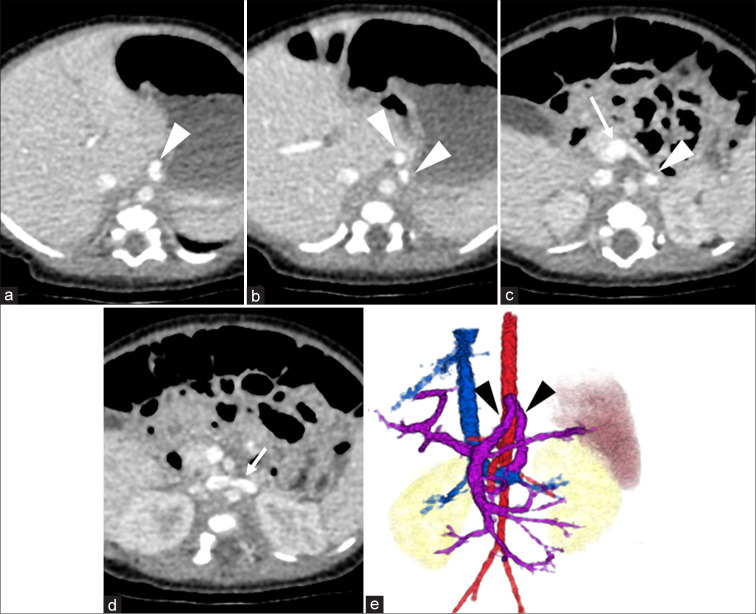

先天性门静脉系统分流(CPSS)是一种罕见的血管异常,其中门静脉血液流入体循环而不经过肝脏。大约每3万到5万例活产婴儿中就有1例。我们报告了一位11岁的肝外CPSS患者,并进行了长期随访。最初的临床表现没有明显的异常。随后的评估显示氨(NH3)和总胆汁酸(TBAs)略有升高。2岁和11岁时两次血管造影证实门静脉和左肾静脉分流,随着患者年龄的增长,血流优势逐渐从腹腔动脉-脾静脉系统转移到肠系膜上动脉-肠系膜上静脉系统。由于并发症的风险,我们进行了经导管分流栓塞,使用12个线圈实现了完全的分流栓塞。栓塞后,NH3和TBA水平恢复正常,患者无症状。该病例强调了CPSS干预时机的重要性,特别是在血流动力学变化的情况下,并强调了儿科CPSS最佳干预时机的进一步研究的必要性。

Congenital portosystemic shunt (CPSS) is a rare vascular anomaly in which portal vein blood flows into the systemic circulation without passing through the liver. They occur in approximately 1 in 30,000-50,000 live births. We present an 11-year-old patient with an extrahepatic CPSS managed with long-term follow-up. The initial clinical presentation showed no significant abnormalities. Subsequent assessments revealed slightly elevated ammonia (NH3) and total bile acids (TBAs). Two times angiography at the ages of 2 and 11 years confirmed a shunt between the portal vein and left renal vein, with a gradual shift in blood flow dominance from the celiac artery-splenic vein system to the superior mesenteric artery-superior mesenteric vein system as the patient aged. Due to the risk of complications, transcatheter shunt embolization was performed, utilizing 12 coils to achieve complete shunt embolization. Post-embolization, NH3, and TBA levels normalized, and the patient remained asymptomatic. This case highlights the importance of timing in CPSS intervention, particularly with shifting hemodynamics and underscores the need for further studies on optimal intervention timing in pediatric CPSS.